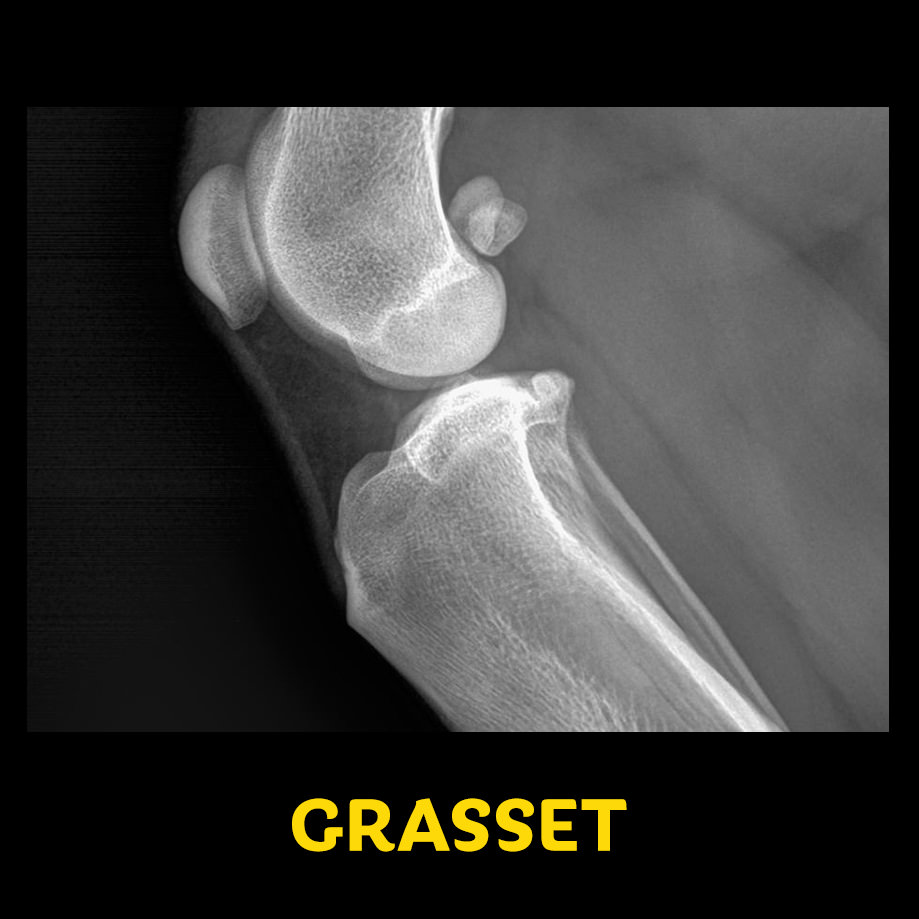

- En latéral pour les membres

- Extrémité distale au bas de l’écran

- Portion proximale au corps au haut de l’écran

- Portion crâniale à gauche de l’écran

- Portion caudale à droite de l’écran